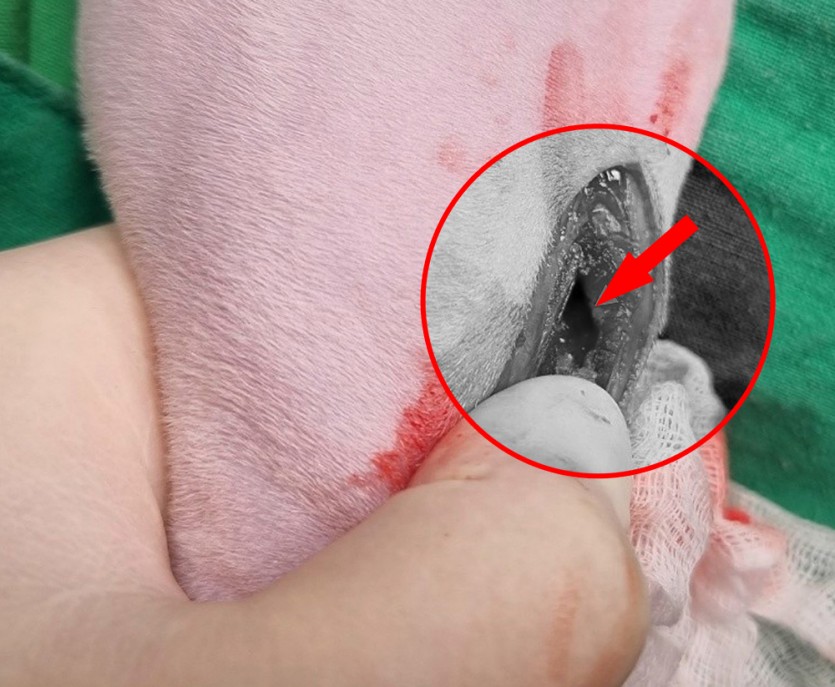

<수술 중 : 골절된 경골조면(화살표)이 확인된다>

5개월령의 어린 아이로 꼼꼼한 마취 전 검사가 진행되었고, 다행히 마취 전 검사 상에 아무런 문제가 없어 수술적인 교정이 진행되었습니다. 수술 중에 경골 조면의 골절선이 확인되었고, 골절선을 잘 맞춘 뒤 핀과 와이어를 이용해 단단하게 고정해주었습니다.